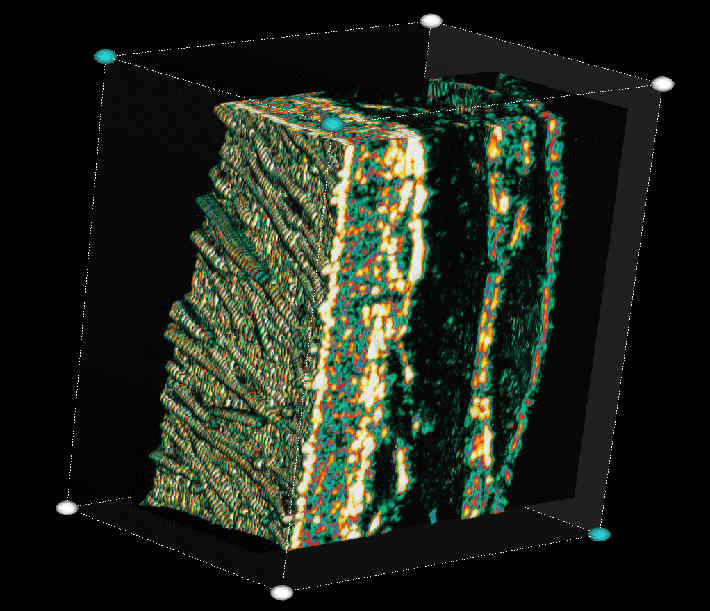

20 MHz 3D images

| Misc. |  Ageband, forearm |

Nevus, skin parallel cut |

Normal, overlying hairs |